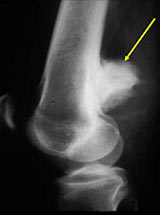

- Posterior distal femur metaphysis (65%)

- Presents as a mass in popliteal fossa

X-Rays:

- Lobulated and ossified exophytic mass (cauliflower-like) adjacent to the cortex; attached to metaphyseal cortex via a broad base

- Centrally, the tumor is radiodense (demonstrates ossification)

- There is no periosteal reaction since the tumor comes from the outer layer of the periosteum and therefore does not elevate the periosteum.